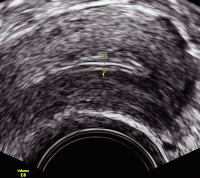

Tipps und Tricks im Gyn-Ultraschall: Das prämenstruelle und das menstruelle Endometrium

Journal für Gynäkologische Endokrinologie 2013; 7 (3) (Ausgabe für Österreich): 24-25 Journal für Gynäkologische Endokrinologie 2013; 7 (3) (Ausgabe für Schweiz): 33-34 Volltext (PDF) Abbildungen